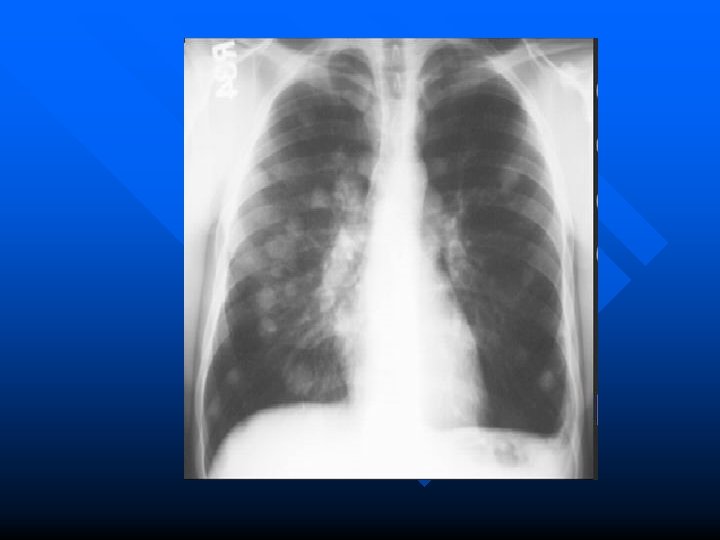

Metastatic tumors Most pulmonary metastases genitourinary and gastrointestinal system. n Hematogenous metastasis Discrete and circumscribed Miliary or snow strom appearance indicated rapid growth. n Lymphatic permeation Mediastinum and its nodes are the first line with this type of spread. n Massive pleural effusion. n